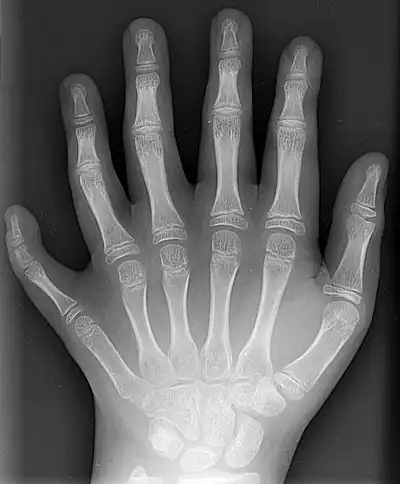

The following are images from various Medicine-related articles on Wikipedia.